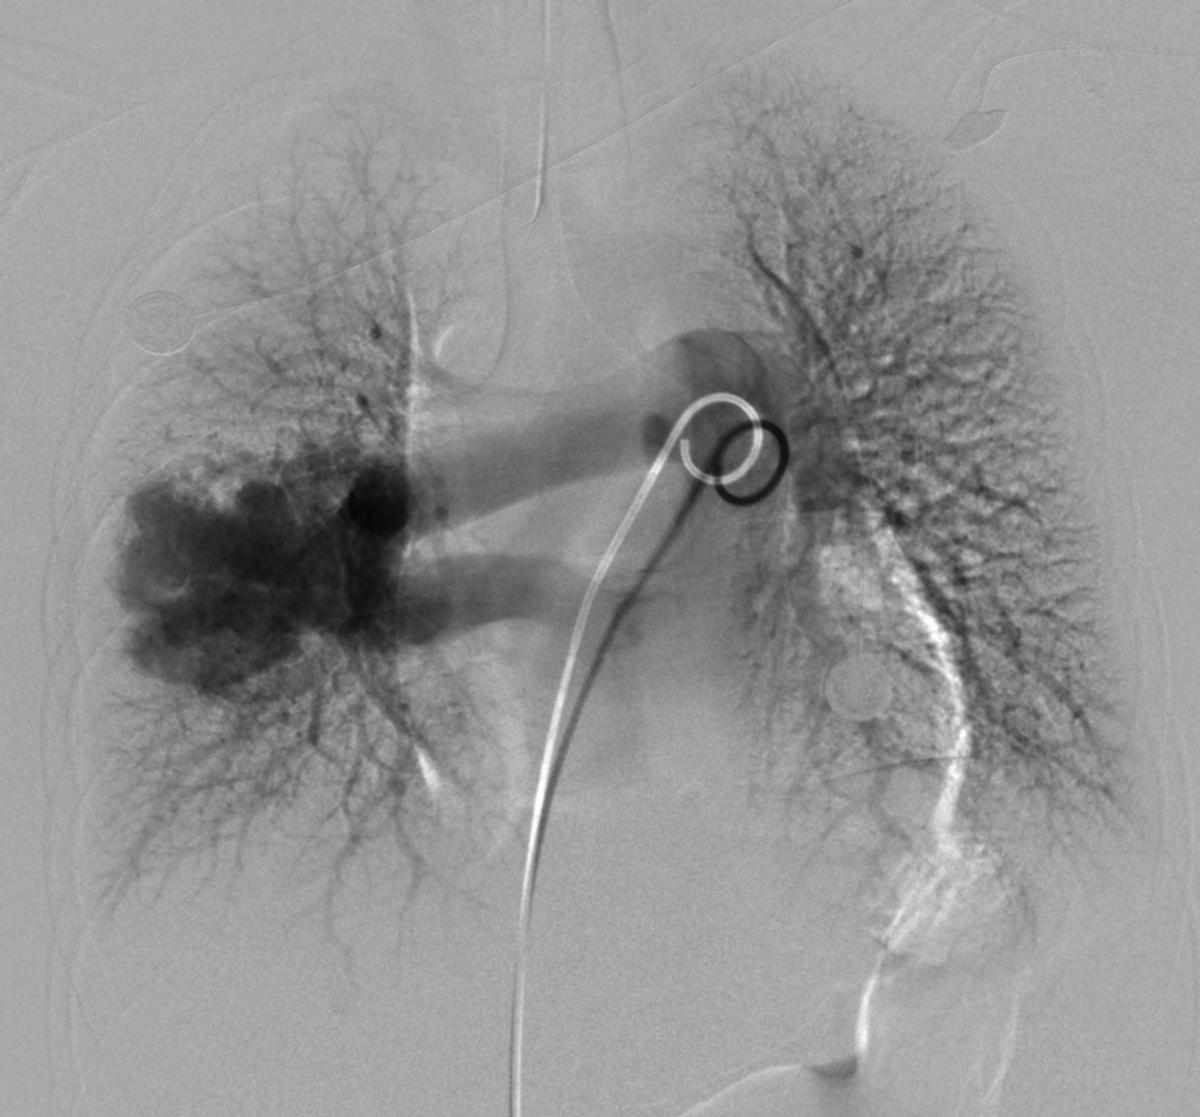

右肺下叶肺动静脉瘘,右下肺动脉扩张连接右肺下叶背段,右肺静脉增粗

弹簧圈栓塞囊腔+供血动脉